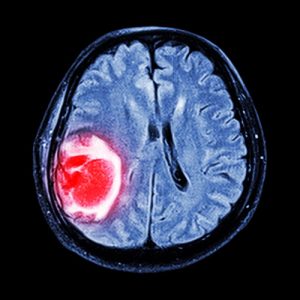

Когда возникает необходимость пройти лечение по поводу рака мозга, большинство людей выбирают Германию. И это неудивительно: клиники Германии давно и прочно укрепились в лидерах рейтинга лечебных учреждений, в которых самые высокие показатели терапии. Многолетняя исследовательская работа и использование технологических новинок позволяют немецким онкологам справляться даже со сложными случаями онкопоражений мозга, выводить пациентов из тяжелых состояний и обеспечивать длительную ремиссию. Залогом успешного лечения является использование таких передовых методик как радиохирургия, микрохирургия, химиотерапия по новейшим стандартам. Лечение опухоли мозга в Германии проходит не только эффективно, но и максимально бережно. Отсутствуют тяжелые осложнения, которые считались нормой, когда использовали более устаревшие методики радиотерапии и химиотерапии, операции проводятся с максимальным сохранением важнейших мозговых центров, отвечающих за речь, движение, координацию и так далее. Новинка современной нейрохирургии – роботизированная хирургическая установка дает возможность не только успешно удалить новообразование, но и сделать это без тяжелых последствий для пациента. Отзывы о лечении рака мозга в Германии подтверждают репутацию немецких онкологов и нейрохирургов как наиболее компетентных и опытных.

Диагностика рака мозга в Германии

Высокая достоверность данных диагностики (до 100%) позволяет немецким врачам выбирать наиболее оптимальные варианты лечения, максимально эффективные и безопасные. Как правило, диагностику проводят врачи-диагносты с большим опытом и уровнем подготовки. Диагностические центры оборудованы высокоинформативной аппаратурой последнего поколения. Некоторые исследования уникальны, например, инновационное ПЭТ-КТ – это способ выявления метастазов на ранних стадиях, когда другие виды исследований не позволяют их фиксировать. Сам процесс диагностики занимает несколько дней, и максимально комфортно для пациента.

- КТ, ПЭТ-КТ

- МРТ.